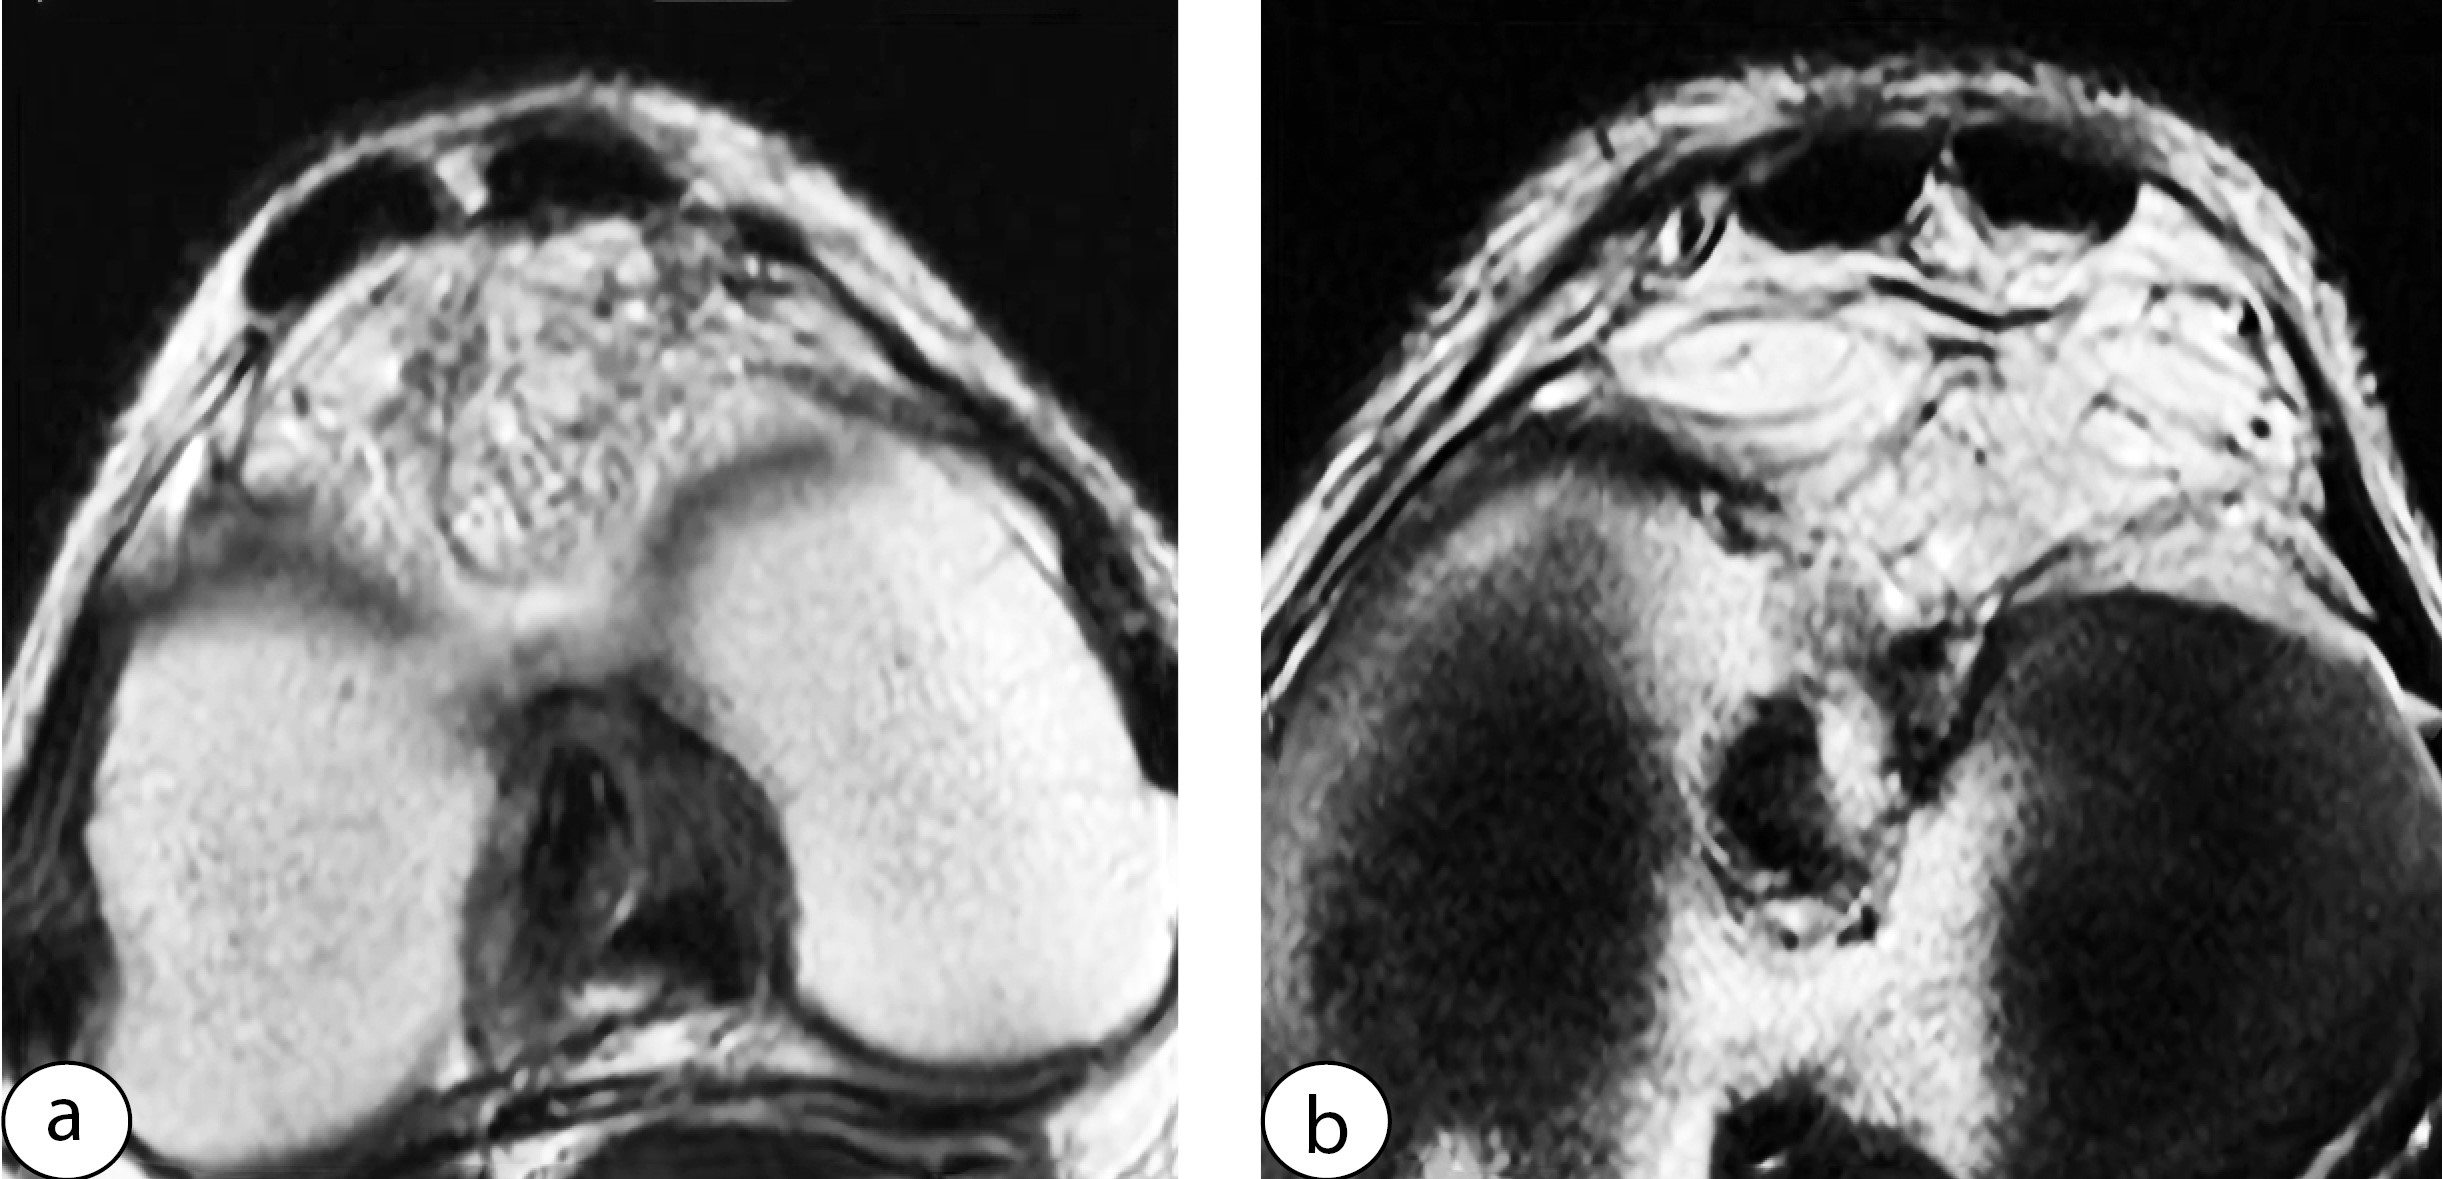

In all patients of the Group 2 who underwent graft harvesting with subsequent full-layer suturing of the defect, the ligament after surgery formed a unified structure. The suture line was either not visible or barely discernible. No tendon defects or deformities due to suture divergence were observed. The width of the ligament was almost completely restored, with only moderate thickening visible on all axial slices (Figure 5).

Figure 5. MRI scan of the patellar tendon in a patient from Group 2 before (a, b) and after graft harvesting (c, d)

Two patients with sutures placed at intervals of more than 2 cm and not across all layers exhibited areas of deformed and incompletely healed ligament (Figure 6).

Figure 6. Appearance of the deformed patellar tendon after graft harvesting with non-full-thickness suturing: tendon edges are approximated but not sutured (a), only the superficial layer and peritenon are sutured (b)